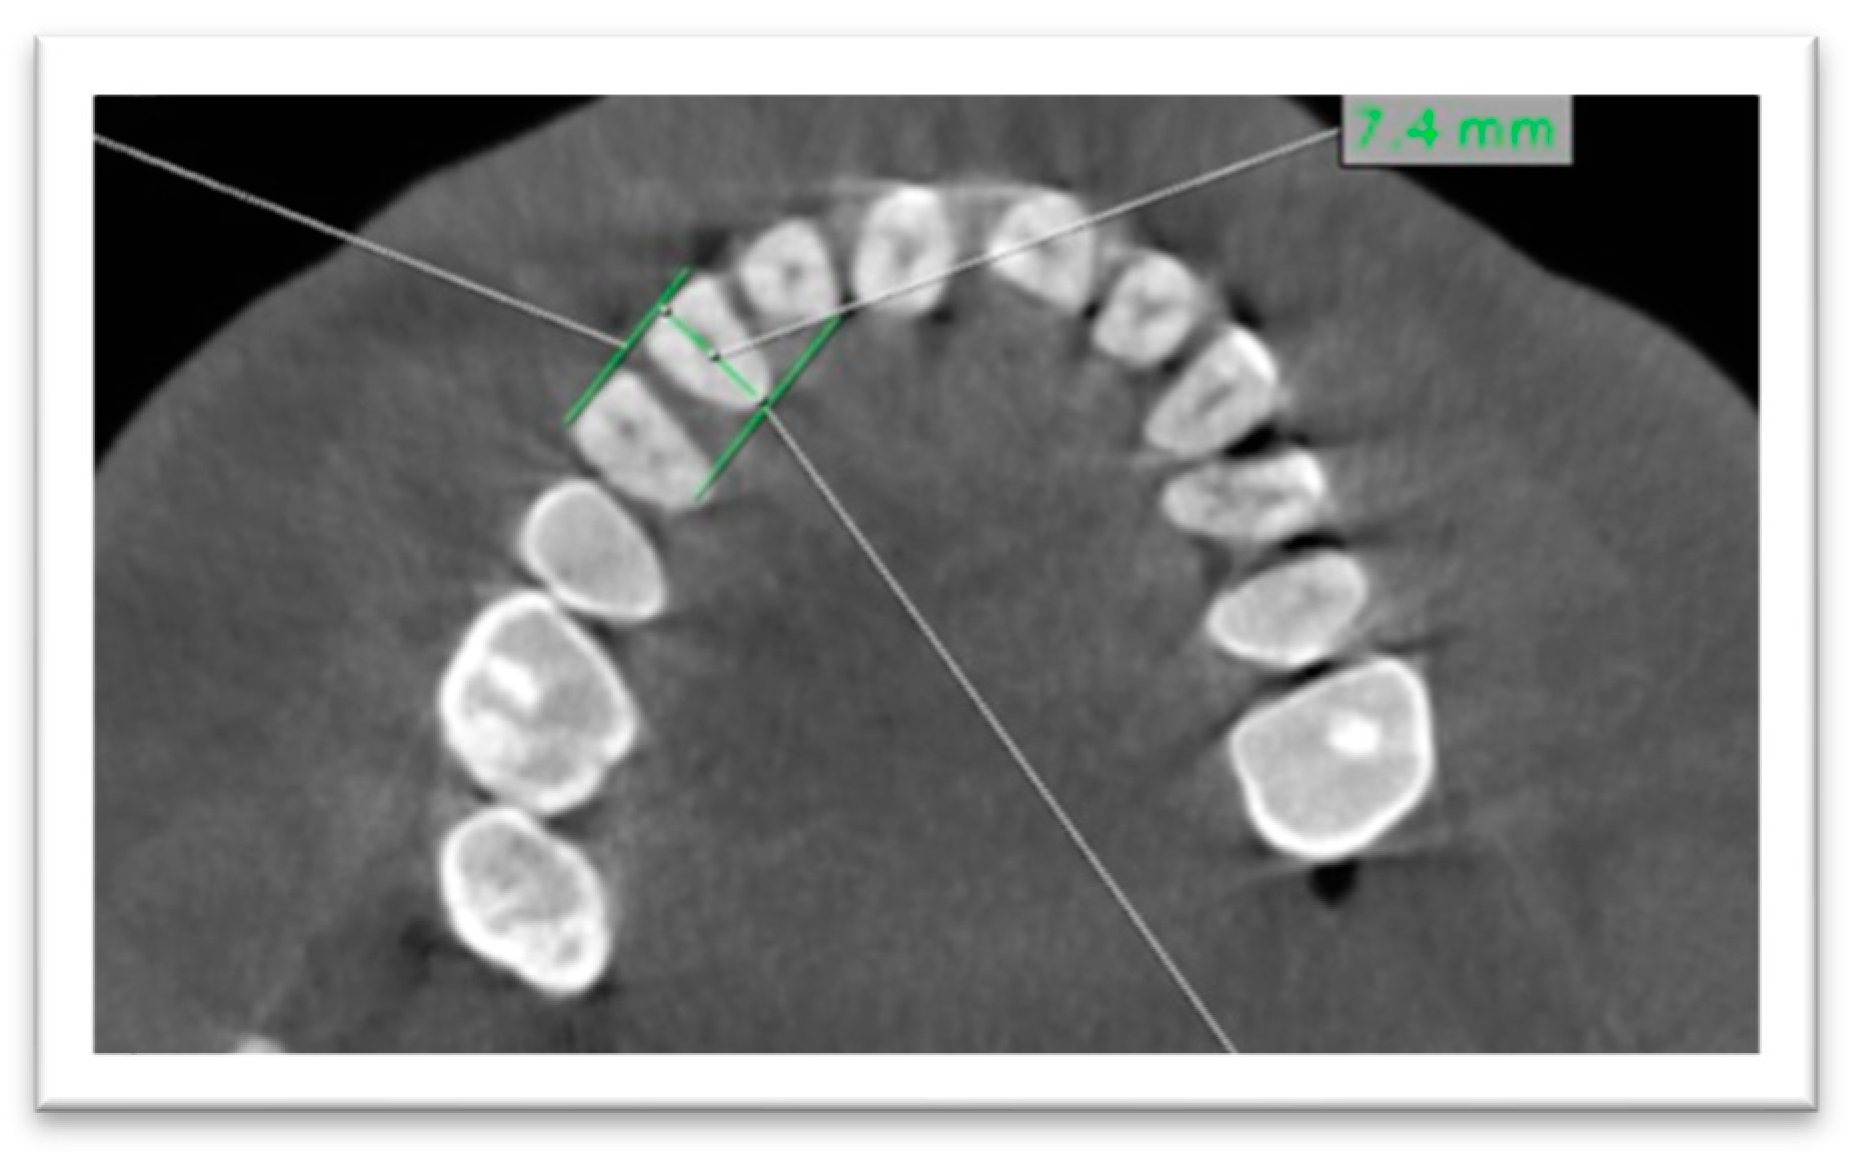

- Regarding buccopalatal diameter, it was measured at the level of CEJ by a line bisecting the tooth on the axial plane (Figure 2).

- Mesiodistal diameter was measured at the CEJ level on the axial plane (Figure 3).